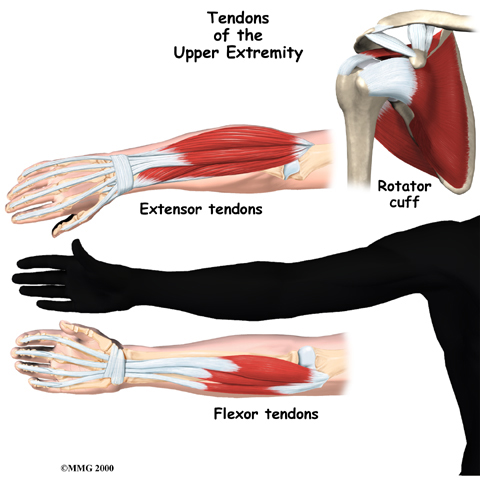

Lateral Epicondylitis -- Tennis Elbow

Lateral epicondylitis or tennis elbow is a painful overuse injury. It involves the inflammation or microscopic tearing of tendons that attach the forearm muscles to the outside of the elbow. Repetitive movements, such as swinging a tennis racquet, can cause this type of injury.

Medial Epicondylitis - Golfer's Elbox

Medial epicondylitis—also known as golfer’s elbow—develops due to inflammation of the tendons that attach the forearm muscles to the inside of the elbow. This type of injury is caused by overuse of the tendons in this region (e.g., repeatedly swinging a golf club). It is associated with tenderness and pain on the inner side of the elbow. Golfer’s elbow can also cause pain in the wrist and hand during movement.

Rotator Cuff Tendonitis

Rotator cuff tendonitis refers to inflammation of the rotator cuff due to repeated stress (e.g., throwing, overhead lifting). This injury is also described as shoulder impingement, biceps tendonitis, or shoulder bursitis. Rotator cuff tendonitis often leads to chronic pain, even while at rest.

The upper portion of the arm bone, called the humerus, is connected to the shoulder by tendons and muscles. Four of these tendon-muscle groups form what is known as the rotator cuff—the structure that stabilizes the shoulder and controls the lifting of the arm.

Rotator cuff problems can range from mild damage to partial or complete tears. If left untreated, a severely torn rotator cuff may require surgical treatment.

Related Document: Ari Levine PT, PC's Guide to Rotator Cuff Disease